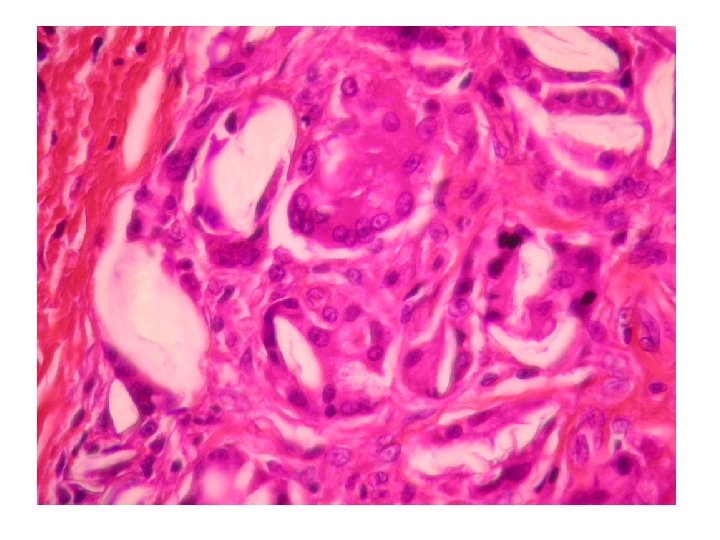

Calcifications dystrophiques: cancer papillaire du poumon

HES Bleu Alcian

HES VON KOSSA